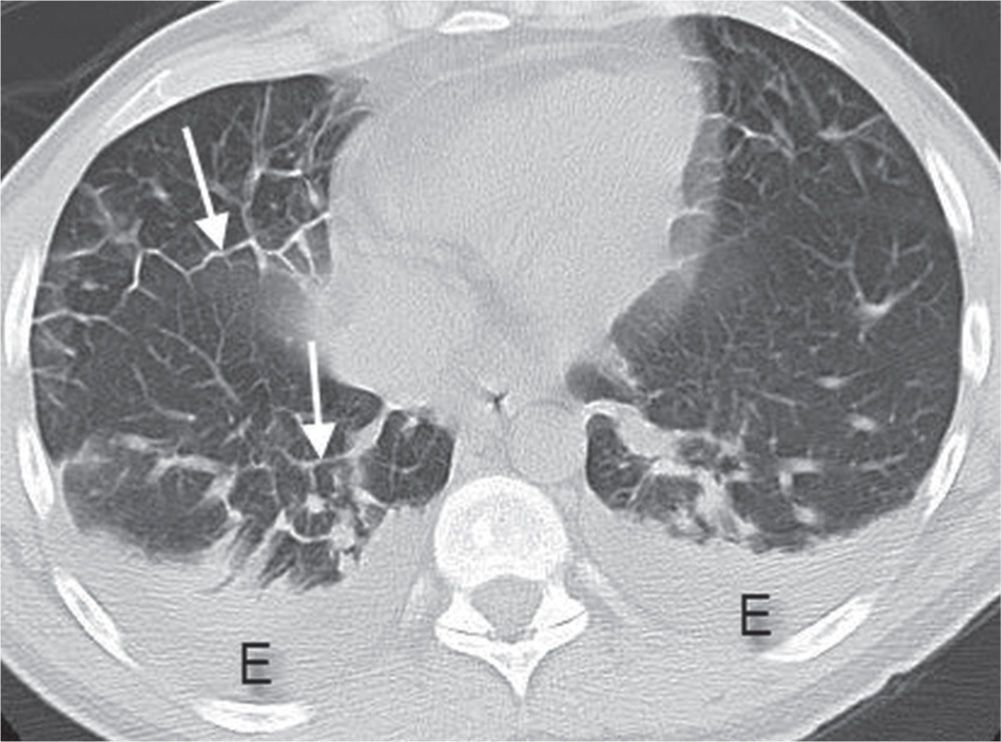

Interstitial lung disease UIP Radiology at St. Vincent's University

From radiologykey.com